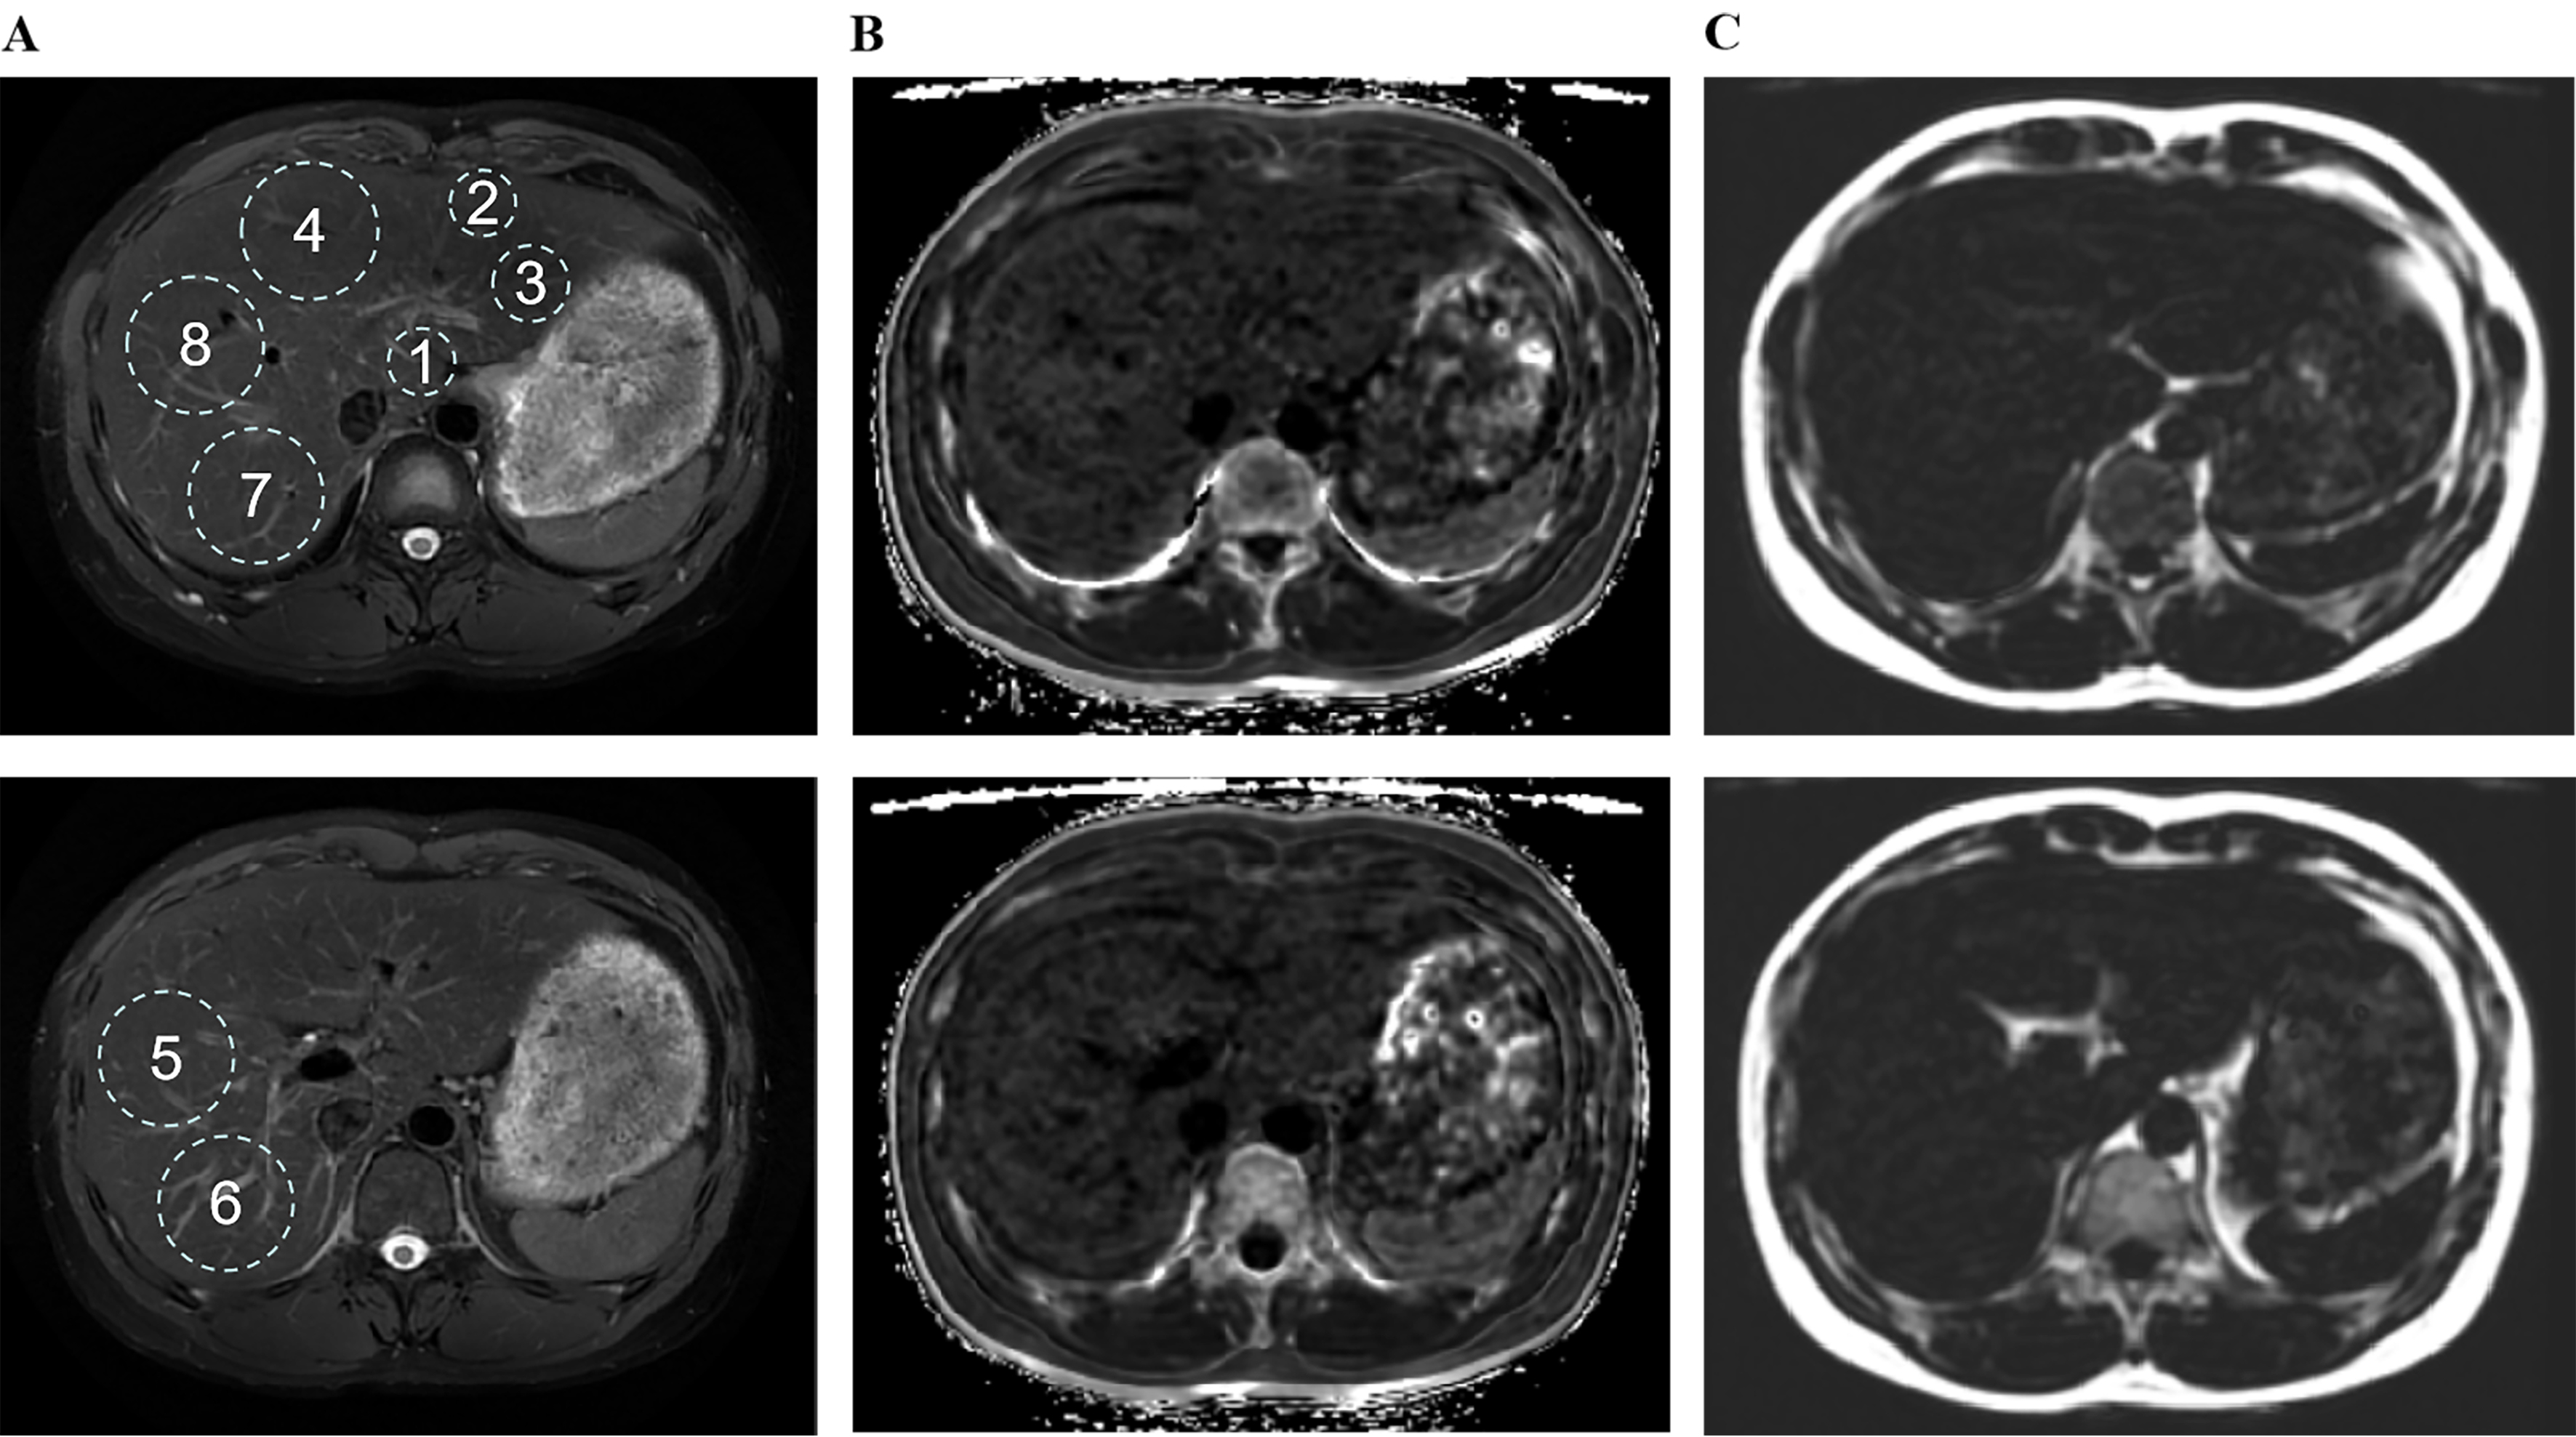

To ensure the repeatability of the region of interest (ROI) localization in liver imaging and neuroimaging analysis, for liver MRI features, the maximum fitting ROI was placed in each of the eight Couinaud liver segments [Figure 2A], carefully avoiding major blood vessels, bile ducts, and obvious image artifacts[17]. The R2* relaxation maps (Hz), reflecting the rate of signal decay caused by both intrinsic tissue properties and magnetic field inhomogeneities, were generated to quantify iron deposition [Figure 2B][18], while proton density fat fraction (PDFF, %) was measured to evaluate hepatic steatosis [Figure 2C][19].

Figure 2. Size, location, and quantity of ROIs numbered 1 to 8 in liver magnetic resonance imaging, using Wilson’s disease patients as a representative example. ROIs for paradigms 1-8 were placed in the largest fit, respectively. (A) RTr-Ax-T2-fs-Prop is utilized to identify anatomical structures; (B) R2 star-BH-IDEAL-IQ is employed for the quantification of iron; (C) FatFrac-BH-IDEAL-IQ is applied for the quantification of fat. ROIs: Region of interest; RTr-Ax-T2-fs-Prop: (specific MRI sequence, name retained from original); R2: the rate of signal decay caused by the combined effects of intrinsic tissue properties and magnetic field inhomogeneities, and were generated to quantify iron deposition; BH: breath hold; IDEAL-IQ: iterative decomposition of water and fat with echo asymmetry and least-squares estimation-iron quantification; FatFrac: fat fraction.